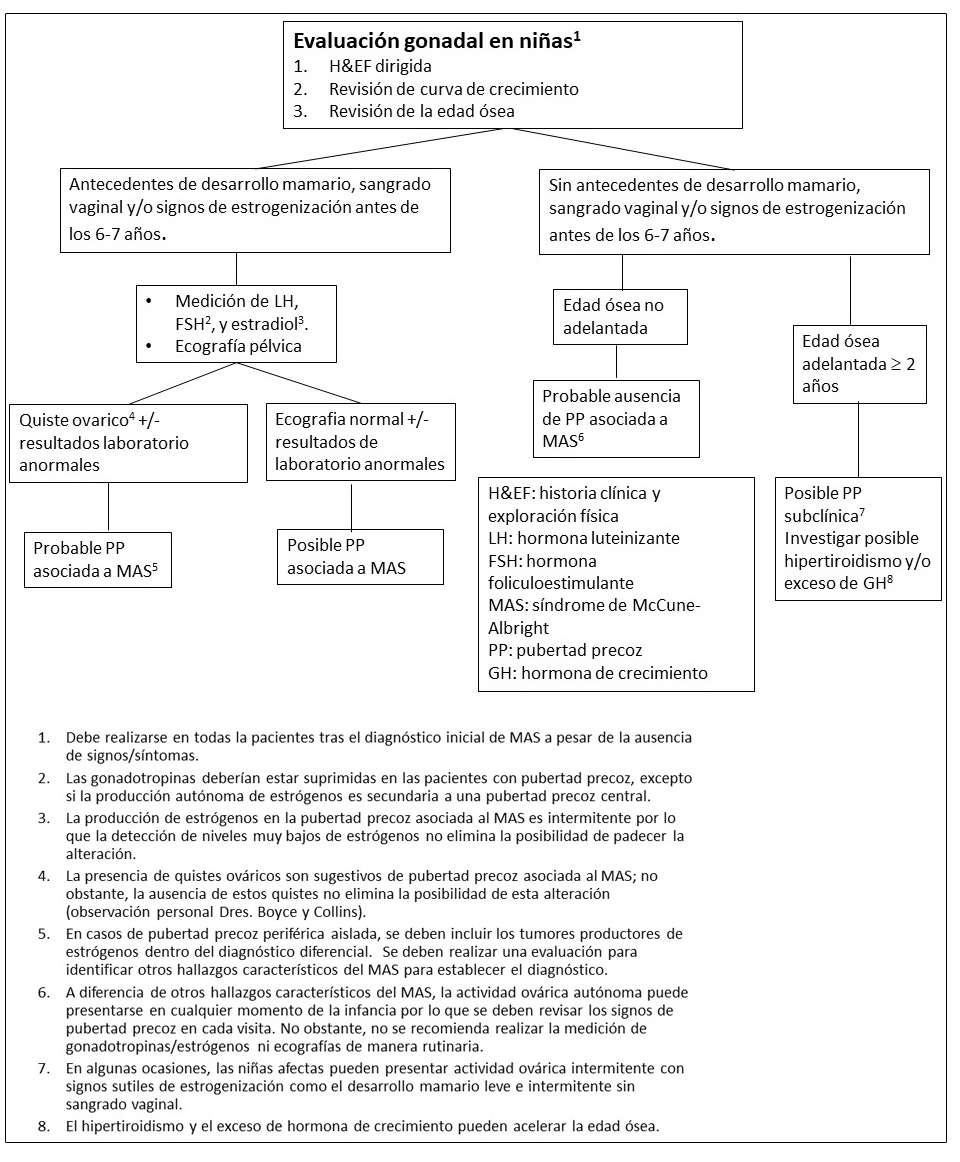

Figura 6. Pruebas y seguimiento recomendado para la evaluación de trastornos gonadales en niñas con Displasia Fibrosa/Síndrome de McCune-Albright

Pubertad precoz.

Es muy frecuente en niñas con DF/MAS (~85%). Es habitual que la pubertad precoz sea el síntoma inicial de la enfermedad. Los quistes ováricos recurrentes (Ver Figura 4A) conlleva la producción intermitente de estrógenos lo cual resulta en el desarrollo de senos, aceleración del crecimiento lineal y sangrado vaginal. Durante los intervalos entre la involución de quistes antiguos y la formación de quistes nuevos, el tejido mamario suele involucionar y los niveles de estrógeno sérico retornan a niveles prepuberales. El desarrollo de quistes ováricos suele continuar en la edad adulta, por lo que es frecuente que las pacientes afectas presenten ciclos menstruales irregulares (Lala et al 2007). La torsión ovárica se ha descrito en raras ocasiones en niñas y mujeres con quistes persistentes de gran tamaño (Clark et al 2000).

La pubertad precoz es menos frecuente en niños con DF/MAS (~10-15%), y es secundaria a la producción autónoma de testosterona (Boyce et al 2012a) resultando en un desarrollo puberal progresivo, incluyendo una aceleración en el crecimiento lineal, crecimiento de vello púbico y axilar, la aparición de acné, y el desarrollo de una comportamiento inapropiadamente agresivo y sexual.

Tanto en niños como en niñas con pubertad precoz, la producción autónoma prolongada de esteroides sexuales generalmente culmina en la activación del eje hipotálamo-hipofisario y en el desarrollo de pubertad precoz central.

Fertilidad.

El efecto de la producción de esteroides sexuales sobre la función gonadal y la fertilidad no han sido adecuadamente caracterizados. Las mujeres con DF/MAS pueden tener quistes recurrentes resultando en periodos irregulares durante la edad adulta (Lala et al 2007). Mientras que muchas mujeres de la cohorte del NIH han conseguido embarazos con éxito, es posible que la interrupción de los ciclos ovulatorios pueda disminuir la fertilidad y aumentar en el tiempo hasta la concepción (observación personal de los autores)

Alteraciones testiculares.

Las alteraciones testiculares están presentes en la mayoría de varones con MAS (~85%), y típicamente se manifiestan como macroorquidismo unilateral o bilateral (Boyce et al 2012a). La exploración ecográfica suele mostrar discretas lesiones hiper e hipoecoicas así como microlitiasis, las cuales corresponden a áreas de hiperplasia de células de Leydig y/o Sertoli (Ver Figura 4B).